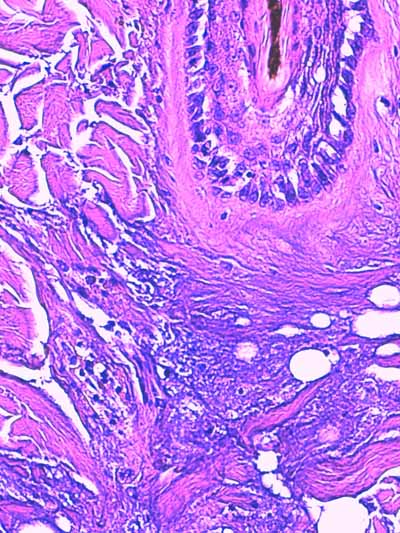

Photo 3 (Hémalun Eosine X 100) : l’épiderme se désengrène, une vésicule

sous-épidermique se forme. Le derme superficiel est œdémateux. Deux plages cellulaires dermiques

sont en étroit rapport avec des annexes folliculo-sébacées, dont une apparaît rompue.

Légendes de la Photo 3 :

- Ovales jaunes : plages cellulaires inflammatoires dans le derme périannexiel

- Flèche turquoise : follicule pileux rompu en rapport avec une plage inflammatoire

- Flèches jaunes : épiderme fragilisé qui se désengrène du derme

- Double flèche orange : épaisseur épidermique

- Double flèche verte : épaisseur dermique

- Double flèche bleue : épaisseur hypodermique

- Flèche orange : une vésicule sous-épidermique se forme

Photo 4 (Hémalun-Eosine X400) : l’épiderme montre des lésions d’œdème cellulaire

et de ballonnisation des acanthocytes, aboutissant à une dégénérescence réticulaire.

Le derme superficiel est œdémateux. Les fibres de collagène sont dilacérées par l’œdème.

Légendes de la Photo 4 :

- Flèches turquoises : fibres de collagène du derme

- Flèches jaunes : œdème et ballonnisation des acanthocytes épidermiques = dégénérescence réticulaire de l’épiderme

- Étoiles rouges : œdème dermique